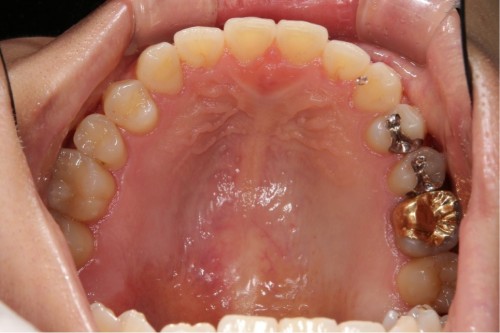

銀歯を白い詰め物に変えました。

左上は虫歯が大きかったのでゴールドインレーで対応してます。見た目はあまり良くありませんが、ゴールドが一番歴史があり信頼できる方法とも言えます。

ゴールドインレー

費用11万円

リスクとして見た目がよくない、汚れがつきやすいことがあげられる。